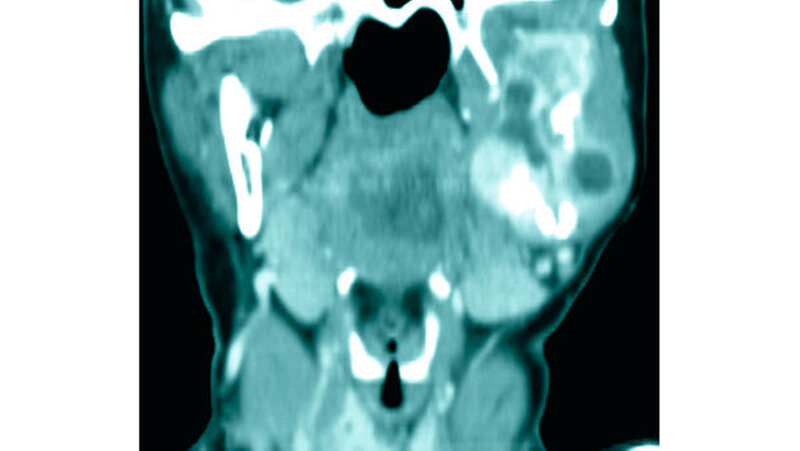

Mit dieser Diagnose wurde die Patientin zur weiteren Therapie in die Mund-, Kiefer-, Gesichtschirurgie der Universitätsmedizin Mainz überwiesen, in der das Staging mittels Computertomografie der Kopf-/Hals-Region sowie des Thorax/Abdomen komplettiert wurde. Hierin zeigte sich lokal eine Ausbreitung bis an den Processus condylaris mit bereits bestehendem Kontakt zum Sinus maxillaris (Abbildungen 4 und 5). Bei pulmonalen Verdichtungen konnte eine Metastasierung nicht sicher ausgeschlossen werden, eine abdominelle Absiedlung bestand nicht.